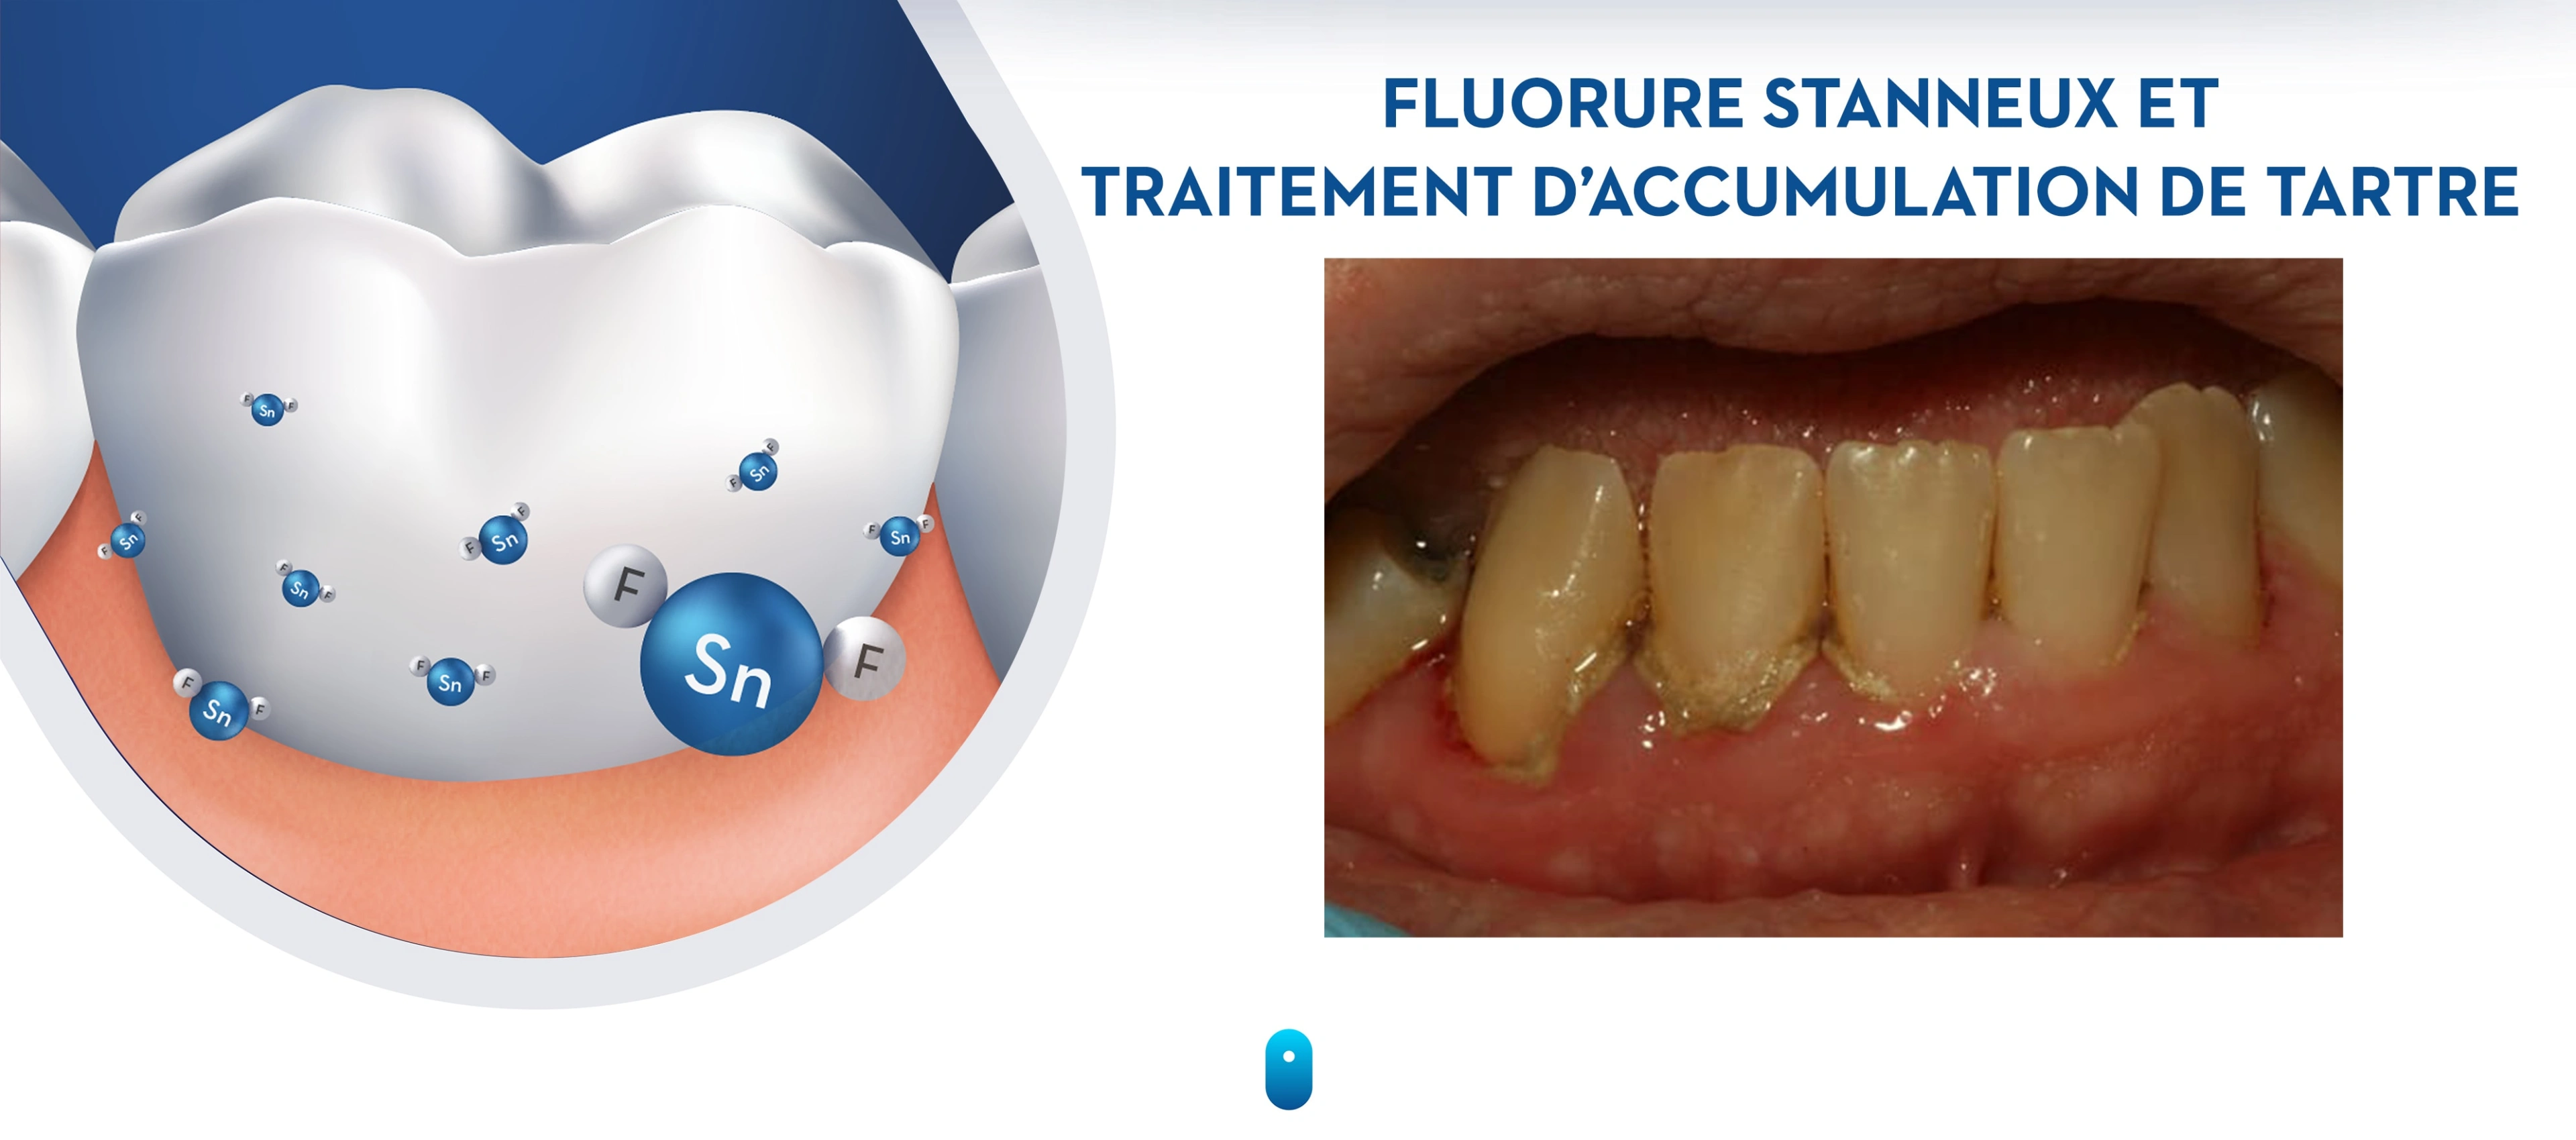

Dental calculus forms through the mineralization of dental plaque, resulting in a variety of different crystalline forms (Sidaway 1978). First, new crystals form, that are composed of calcium and phosphate, which then grow and harden into calculus (Figures 18-19). The mineral content for supragingival and subgingival calculus is on average 37% and 58% by volume, respectively (Friskopp & Isacsson 1984). Supragingival calculus also contains bacterial debris and toxins as well as viable aerobic and anaerobic bacteria (Tan et al. 2004a; Tan et al. 2004b; White et al. 1997). This is of clinical significance as it can be a reservoir of pathogenic bacterial species (Tan et al. 2004b). Dental calculus is common in adults, and less common in children (Anerud et al. 1991).

Figure 18. Formation of dental calculus

Figure 18. Formation of dental calculus